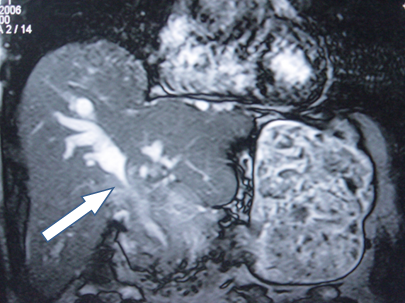

- Zədələnmələrin olub-olmamasını, yеrini və xaraktеrini dəqiqləşdirmək üçün xolangioqrafiya еdilir. MRT ilk seçimdir, lakin dəqiqləşdirmə üçün adətən kontrastlı xolangioqrafiya edilir: əməliyyat vaxtı əməliyyatdaxili xolangioqrafiya, əməliyyatdan sonra isə endoskopik və ya perkutan xolangioqrafiya.

- Öd yollarına yeridilən kontrastın kənara çıxması və ya “blok” (bağlanma) zədələnməni təsdiqləyən əlamətləridir.

Diaqnostik əlamətlər:

- Biliar sızıntı (peritonit, fistul, bilioma, qaraciyərdaxili abseslər) və / və ya mexaniki sarılıq

- Xolangioqrafiyada biliar ekstravazasiya və ya blok

Əməliyyatdan sonra tapılan bağlamalarda xəstə ixtisaslaşmış klinikaya göndərilir. Belə xəstələrdə ilk olaraq MRT edilərək bağlanma yeri dəqiqləşdirilir. MRT yetərsiz olarsa ERXPQ edilə bilər. Əlavə olaraq KT angioqrafiya və ya dopler USM ilə arteriya zədələnməsini yoxlamaq lazımdır. Diaqnostik işləmlərdən sonra zədələnmə yerinə və ağırlaşmalara görə müalicə taktikası seçilir. Magistral axacaqların bağlanmasında xəstə nəzarət altında saxlanılır, anastomoz üçün 2-3 həftə gözlənilir və ağırlaşmaların profilaktikası həyata keçirilir. Bu müddət öd yollarının genişlənməsi, divarının qalınlaşması, iltihabın sönməsi və anastomoz üçün əlverişli şərait yaratmaq məqsədi daşıyır. Gözləmə müddətində ağırlaşmaların profilaktikası və müalicəsi üçün aşağıdakı tədbirlər həyata keçirilir: